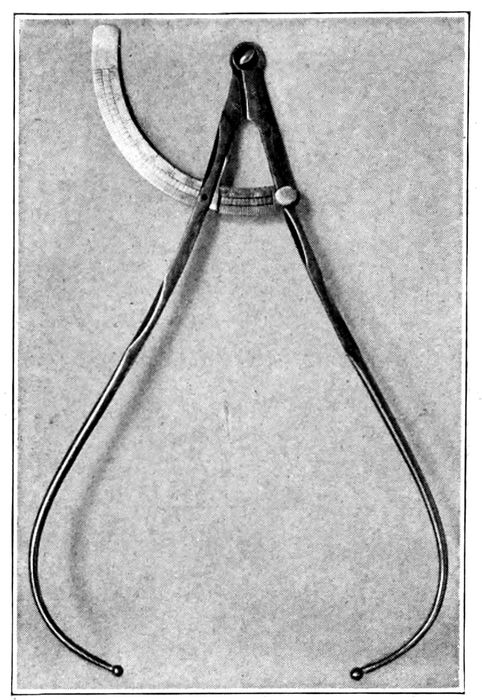

| 94. |

216 |

| 95. |

216 |

| 96. |

217 |

| 97. |

218 |

| 98. |

219 |